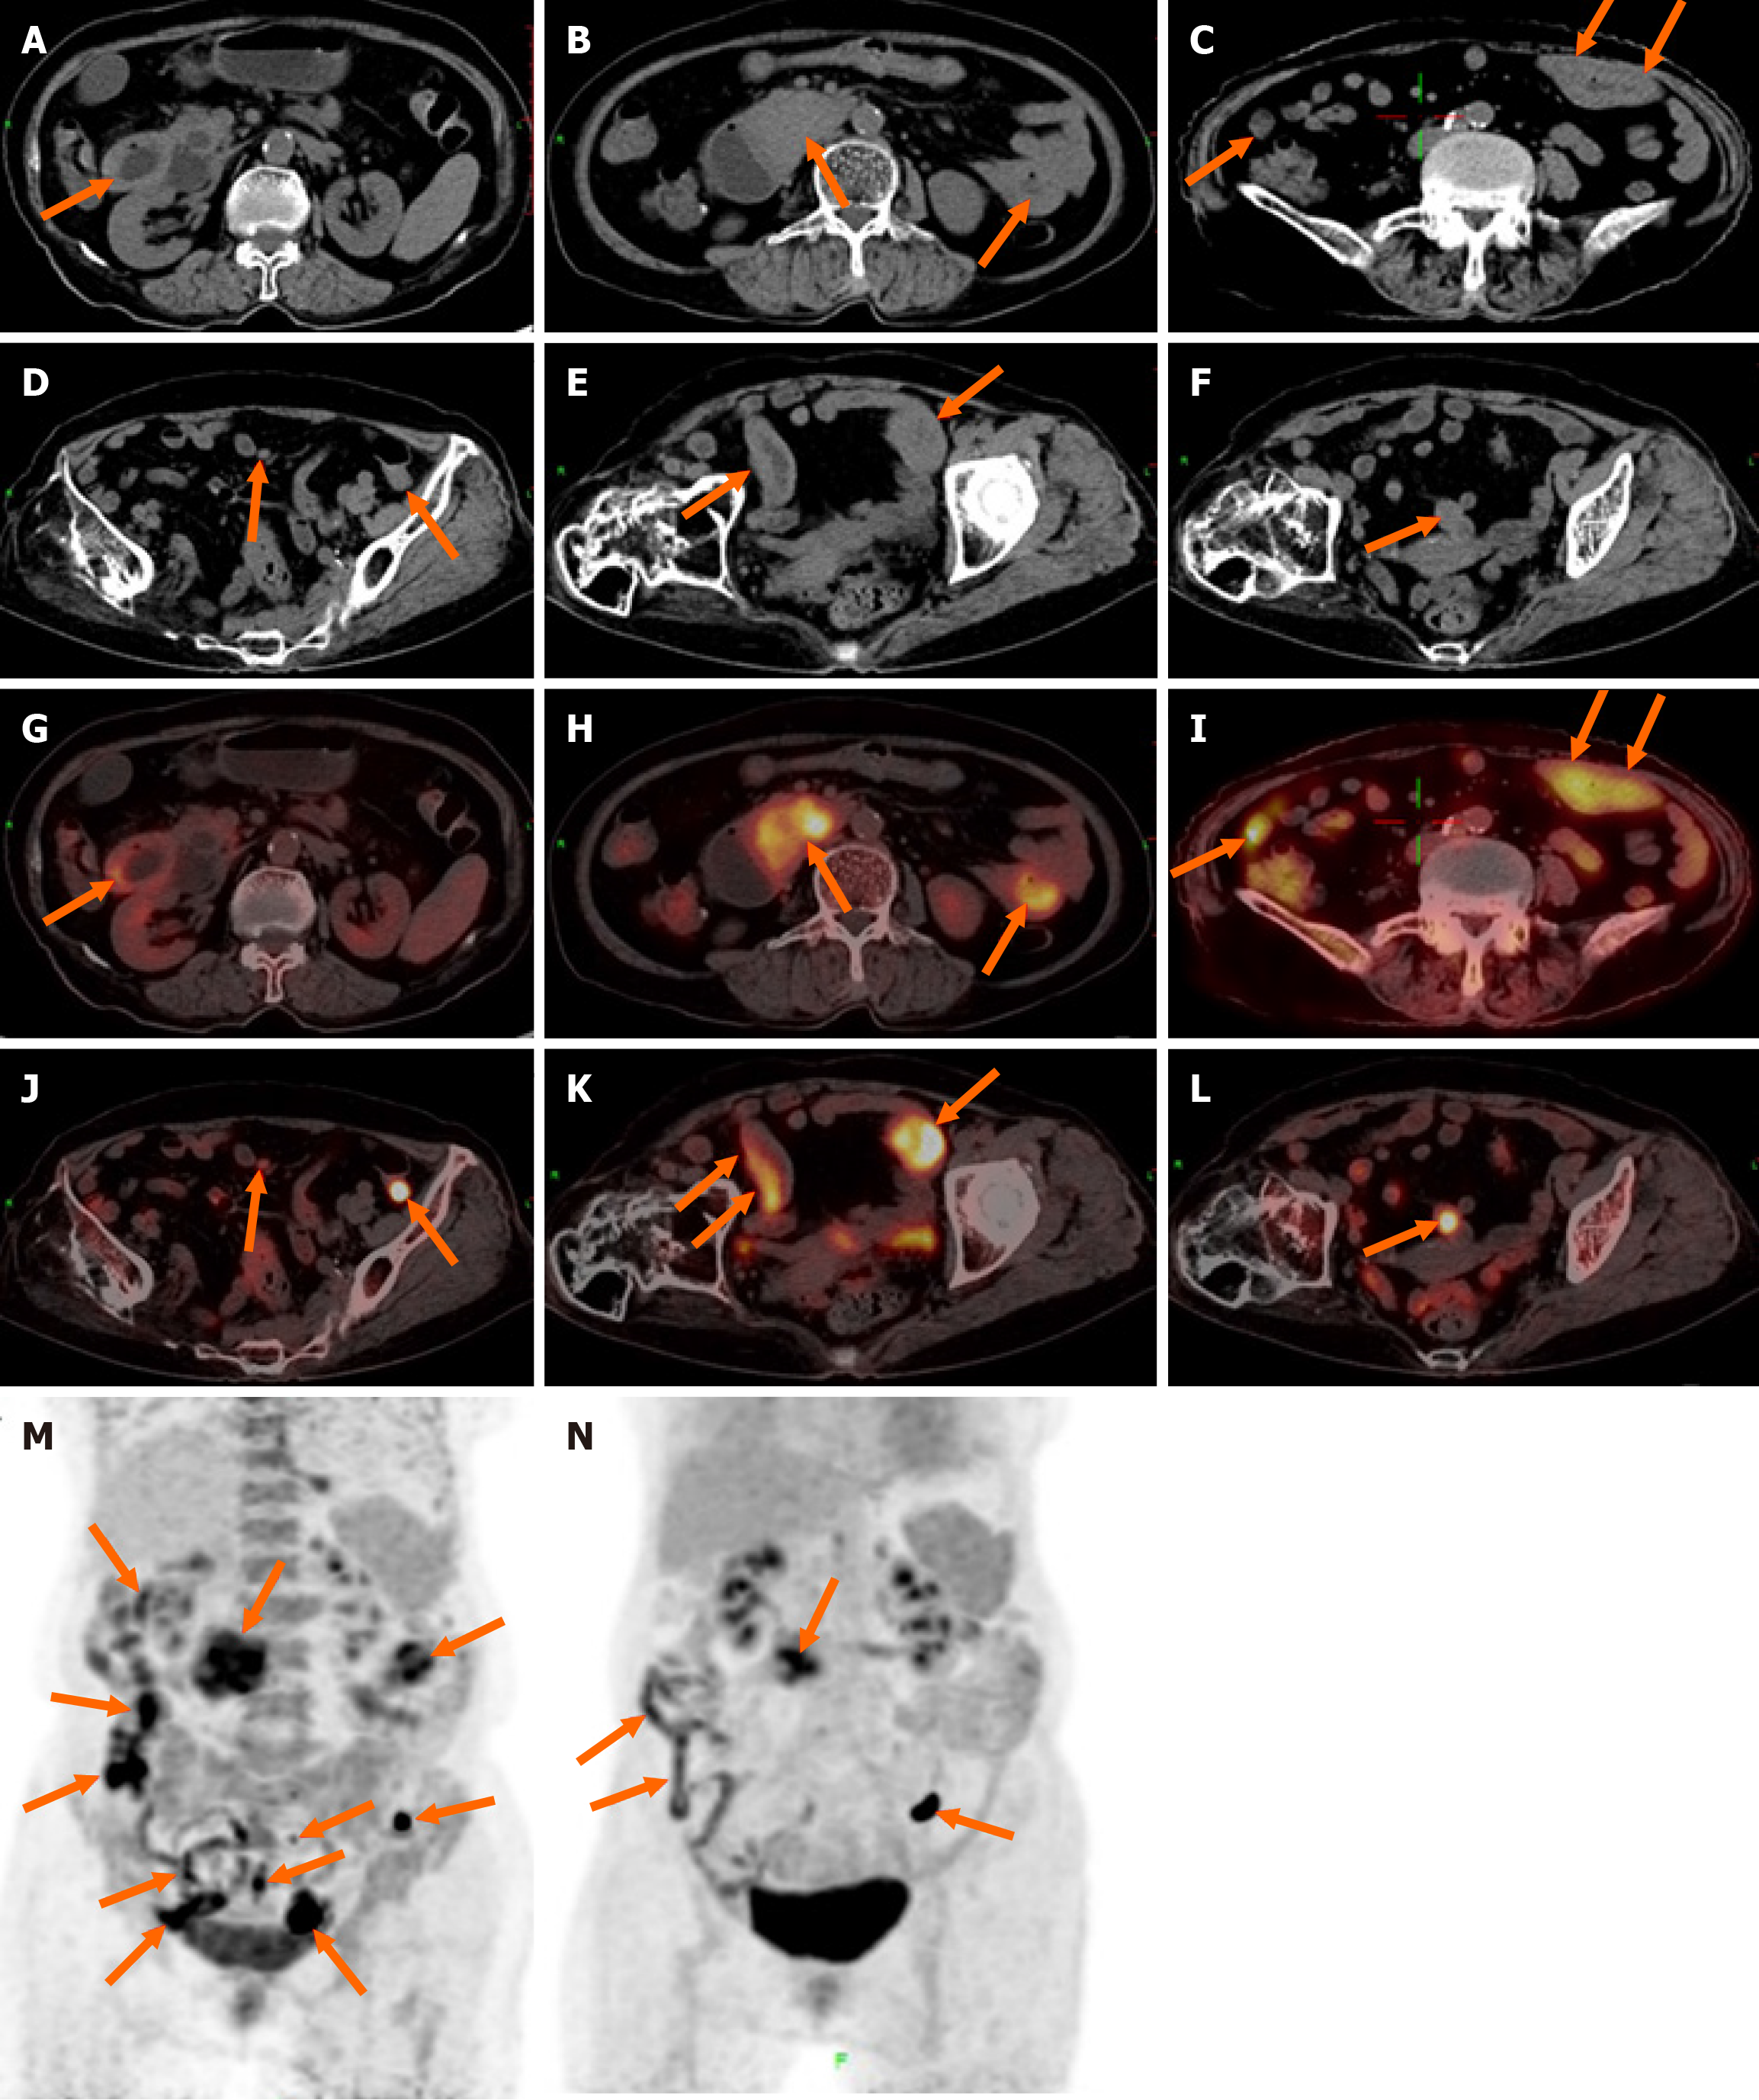

18F-FDG PET/CT revealed multiple segmental thickening in the descending and horizontal segments of the duodenum, jejunum, and ileum. The horizontal segment of the duodenum had the largest lesion, approximately 5 cm × 4 cm in size. The intestinal tract showed aneurysmal dilatation with stenosis and obstruction of the intestinal lumen, and the maximal standardized uptake value (SUVmax) was 9.2 (Figure 1). The SUVmax reflects the uptake of 18F-FDG and the metabolic activity of the lesion. Multiple enlarged lymph nodes were found in the abdominal and pelvic mesentery. The largest lesion was 0.9 cm × 0.7 cm in size, with an SUVmax of 3.1 (Figure 1). A plain MR scan of the upper abdomen revealed that the larger lesion in the horizontal segment of the duodenum presented an iso-signal on T1 weighted imaging (T1WI) and an iso- or hypo-signal on T2WI. It was hyperintense on diffusion-weighted imaging, and the apparent diffusion coefficient was 0.8 × 10-3 mm2/second. Post-contrast MR imaging (MRI) demonstrated delayed and homogeneous enhancement (Figure 2). Gastroduodenoscopy revealed cauliflower-like masses in the duodenal lumen, marked narrowing and obstruction of the intestinal lumen (Figure 3).

The final pathology diagnosis revealed MEITL (Figure 4). 18F-FDG PET/CT revealed retroperitoneal and mesenteric lymph node metastasis. According to the Lugano staging criteria, version 2014, the stage was II.

After the first course of chemotherapy, the patient’s clinical symptoms were significantly relieved. After completing three cycles of chemotherapy, the patient underwent a follow-up 18F-FDG PET/CT scan, revealing a decrease in multiple lesions in the small intestine as well as a reduction in the enlarged mesenteric lymph nodes (Figure 1). The efficacy was evaluated as a partial response. The patient was still alive after 6 months of follow-up.

Currently, there are few imaging reports on MEITL. The previously reported cases are shown in Table 1. According to previous reports, MEITL can involve the whole intestine, with increased FDG uptake in the lesion and an SUV ranged 3.3 to 10.2[8]. Our patient also presented with multiple lesions in the small intestine, with a SUVmax of 9.2, which is consistent with previous reports in the literature. Intestinal lymphoma typically does not involve organ metastasis. However, in rare instances, MEITL may metastasize to the lung, liver, central nervous system and bone marrow[8-11]. MR examination shows iso- or hypo-signals on T2WI and limited diffusion on diffusion-weighted imaging, which is attributable to the abundance of tumor cells and the diminished concentration of extracellular fluid. On an enhanced scan, MEITL exhibits delayed and homogeneous enhancement, which is similar to the performance in a previous report[8]. These findings suggest that MEITL is generally characterized by the absence of necrosis. A search of the PubMed database found five case reports of MEITL that presented with MRI and/or 18F-FDG PET/CT findings (Table 1)[8-10,12,13].

MEITL should be differentiated from Crohn’s disease (CD), intestinal B-cell lymphoma and intestinal carcinoma in imaging diagnosis. The present patient presented with multiple segmental thickening of the small intestine, similar to the imaging findings of “skip distribution” in patients with CD. Although CD also manifests as intestinal wall thickening and FDG uptake, there is no obvious intestinal dilatation. Epelboym et al[14] reported that the average SUV ratio (SUVmax/liver SUVmean) in eight patients with CD before treatment was 3.16 (range 1.88-4.6). The SUV ratio in our patient was 5.4, which was greater than that in patients with CD. On contrast-enhanced CT, CD may present enlargement and thickening of the mesenteric vessels. Moreover, the onset of CD is gradual, and the course of the disease is relatively long, CD can be complicated by abscesses and fistula formation and can involve extraintestinal organs, such as the mouth, eyes and joints[15]. The characteristic finding of CD under endoscopy is cobblestone-like ulceration[15]. Most intestinal B-cell lymphomas are localized lesions, and the SUVmax (mean ± SD) of B-cell lymphoma (14.1 ± 6.4) is significantly greater than that of T-cell lymphoma (7.6 ± 3.9)[16], which is helpful for their differentiation. The focus of intestinal carcinoma is relatively limited, causing focal intestinal concentric stenosis or asymmetric intestinal stenosis. Intestinal carcinoma rarely involves multiple segments; however, it is prone to invade the surrounding fat space and adjacent organs and hematogenously metastasize to the liver and lungs. MEITL is more likely to manifest as aneurysmal dilatation at multiple sites and generally does not result in fat space infiltration around the intestine.

The imaging differential diagnosis of MEITL from ETAL is difficult because of their rarity and limited reference data. On PET/CT, EATL typically presents as hypermetabolic lesions (SUVmax of 6.4-8.0), combined with a background of diffuse low FDG uptake (SUVmax of 2.2-4.6) related to celiac disease[17]. However, MEITL lesions present as discrete hypermetabolic lesions without a background of low FDG uptake, as they are not associated with celiac disease[12]. The final diagnosis depends on pathological examination. There is an absence of standard treatment guidelines for MEITL because of its rarity. In previous reports, cyclophosphamide, doxorubicin, vincristine, and prednisone was the most commonly used chemotherapy[18]. For elderly EMITL patients, our reduced-dose CVP chemotherapy regimen also appeared to be an appropriate treatment, and the patient achieved a partial response after treatment. However, further follow-up studies with larger sample sizes are needed.